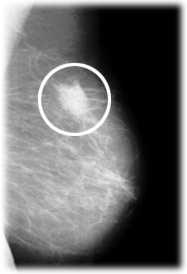

Die Mammographie ist eine Röntgenuntersuchung der Brust.

Sie ist eine zuverlässige Methode um eine Krebserkrankung und deren Vorstufen zu erkennen.

Die Abbildung zeigt einen krebsverdächtigen Knoten in der linken Brust.